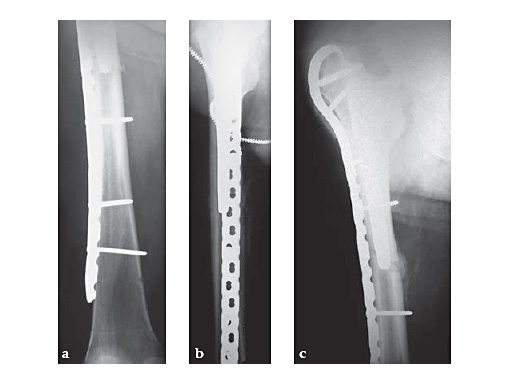

The plate is also useful for ipsilateral combinations of the above patterns with shaft fractures. Nonunions and malunions in this region that meet the criteria of compressibility are also well suited to this plate.

An additional important indication is periprosthetic fracture about the femoral component of a total hip arthroplasty. The trochanteric fixation of the plate (both hook and screws) affords improved proximal fixation, in many cases limiting the need for circlage wires and screws angled around the stem. Compression of primary fracture planes remains desirable in the periprosthetic setting, but is often not possible and does not limit the utility of the plate in this clinical setting. The Plate is available in lengths of 133385 mm, or 216 holes.

83-year-old maletrapped under tree he had cut downIDDM, HTN, CAD, etcJehovahs witnesson Plavix

Case provided by Keith Mayo, Tacoma, USA